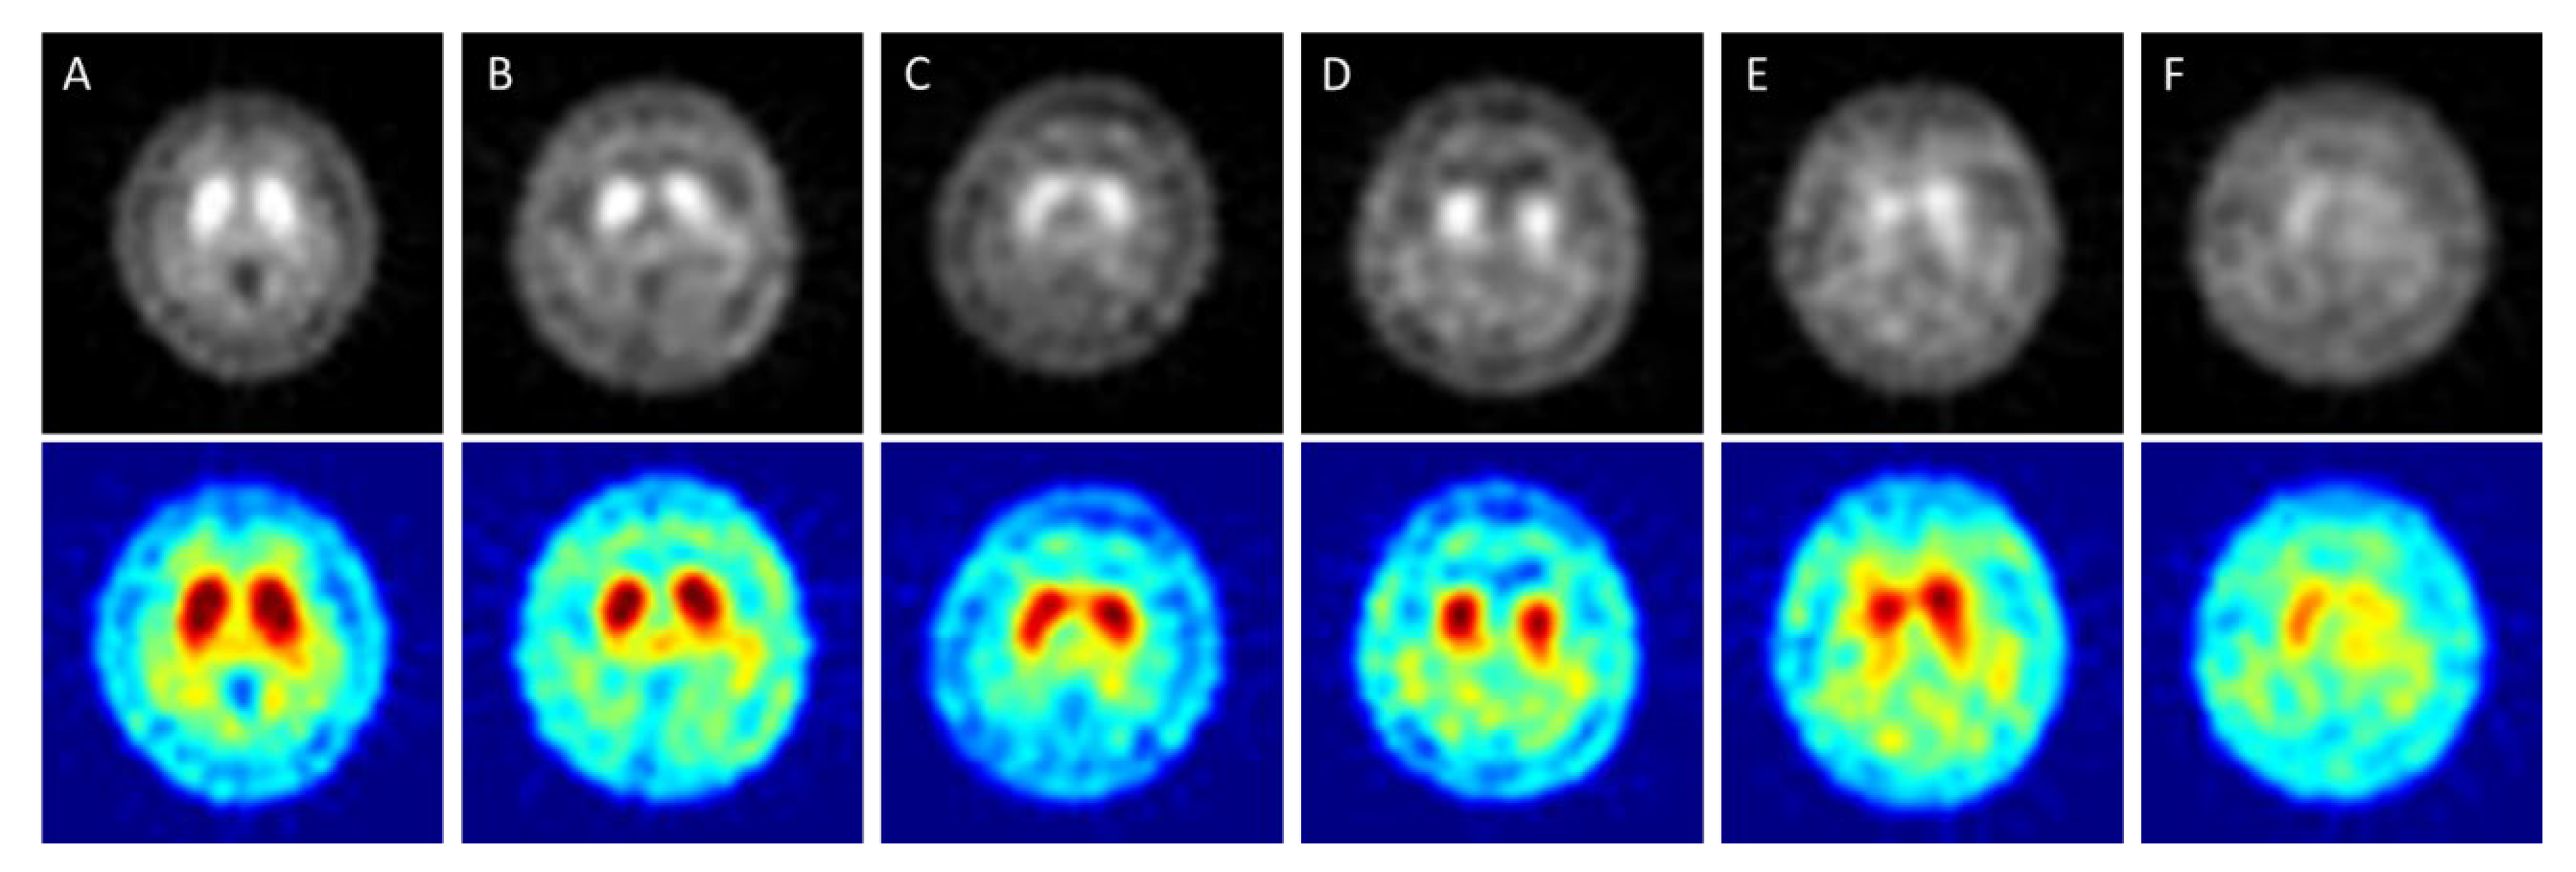

2.2. The Imaging Conditions of 99mTc TRODAT-1 SPECT

- When using deep convolutional neural network technology to classify 99mTc-Trodat-1 PD images for the original grayscale images processed through five pre-trained models (AlexNet, GoogLeNet, VGG19, ResNet, DenseNet201) the highest accuracy was 0.83 for AlexNet. In six categories (healthy, HYS I~V), the best accuracy was 0.78 obtained by VGG19 in four categories (healthy, early, mid, late);

- For color images, DenseNet201 yielded the highest accuracy of 0.85 in four categories. In six categories, the highest accuracy was 0.78 also obtained using DenseNet201;

- Overall, the pre-trained models could produce accurate results when using grayscale images. In this case, the pseudocolor images might be non-essential;